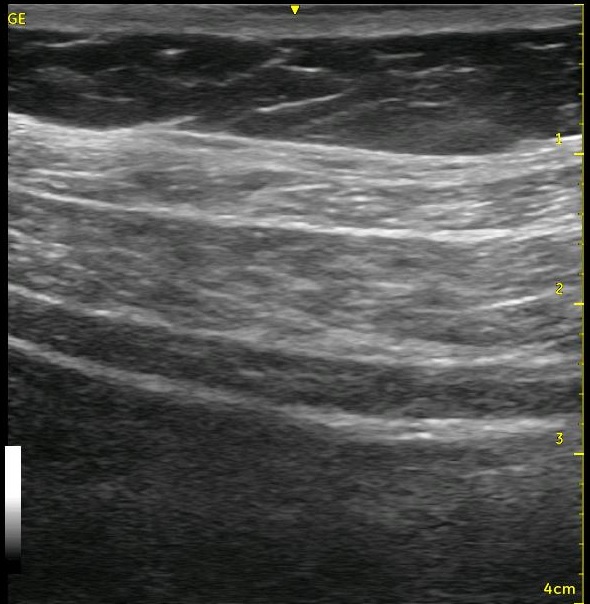

Sometimes, you can’t get the needle right where you want it, or a few confirmatory injections of local anesthetic distorts the local ‘architecture’ of the tissue. If you have done lots of TAP blocks, this has happened to you without question! You start with an awesome image, and end up with something like the image below.

I always say that ultrasound should be used like a video, not just as a picture. The thin slice where the needle lies only gives you a very small view of what is happening within the tissues. If you are having trouble recognizing whether the spread is extending as it should, slide your probe to the ‘periphery of the spread’ where the architecture is still fully intact and visualize the spread from this location. You are starting from pristine architecture and visualizing the changes as you approach your injection site, and you will be able to see whether the local is going where you want it to go or not. Start from the pristine image and slide back toward your original position to see the changes that occur. This may be enough information for you to confirm that you are, in fact, in the correct position, and you can return to your bolusing process. [nonmember]

Look at the images below. They appear to be a series of pictures arranged from the beginning of an injection to the end. In fact, no further injection is added. The first image is taken at the periphery of a TAP block, and the subsequent images are taken as the probe is slid closer to the center of the injection. They confirm that the needle is adequately placed within the appropriate plane though the central position is a bit difficult to interpret.